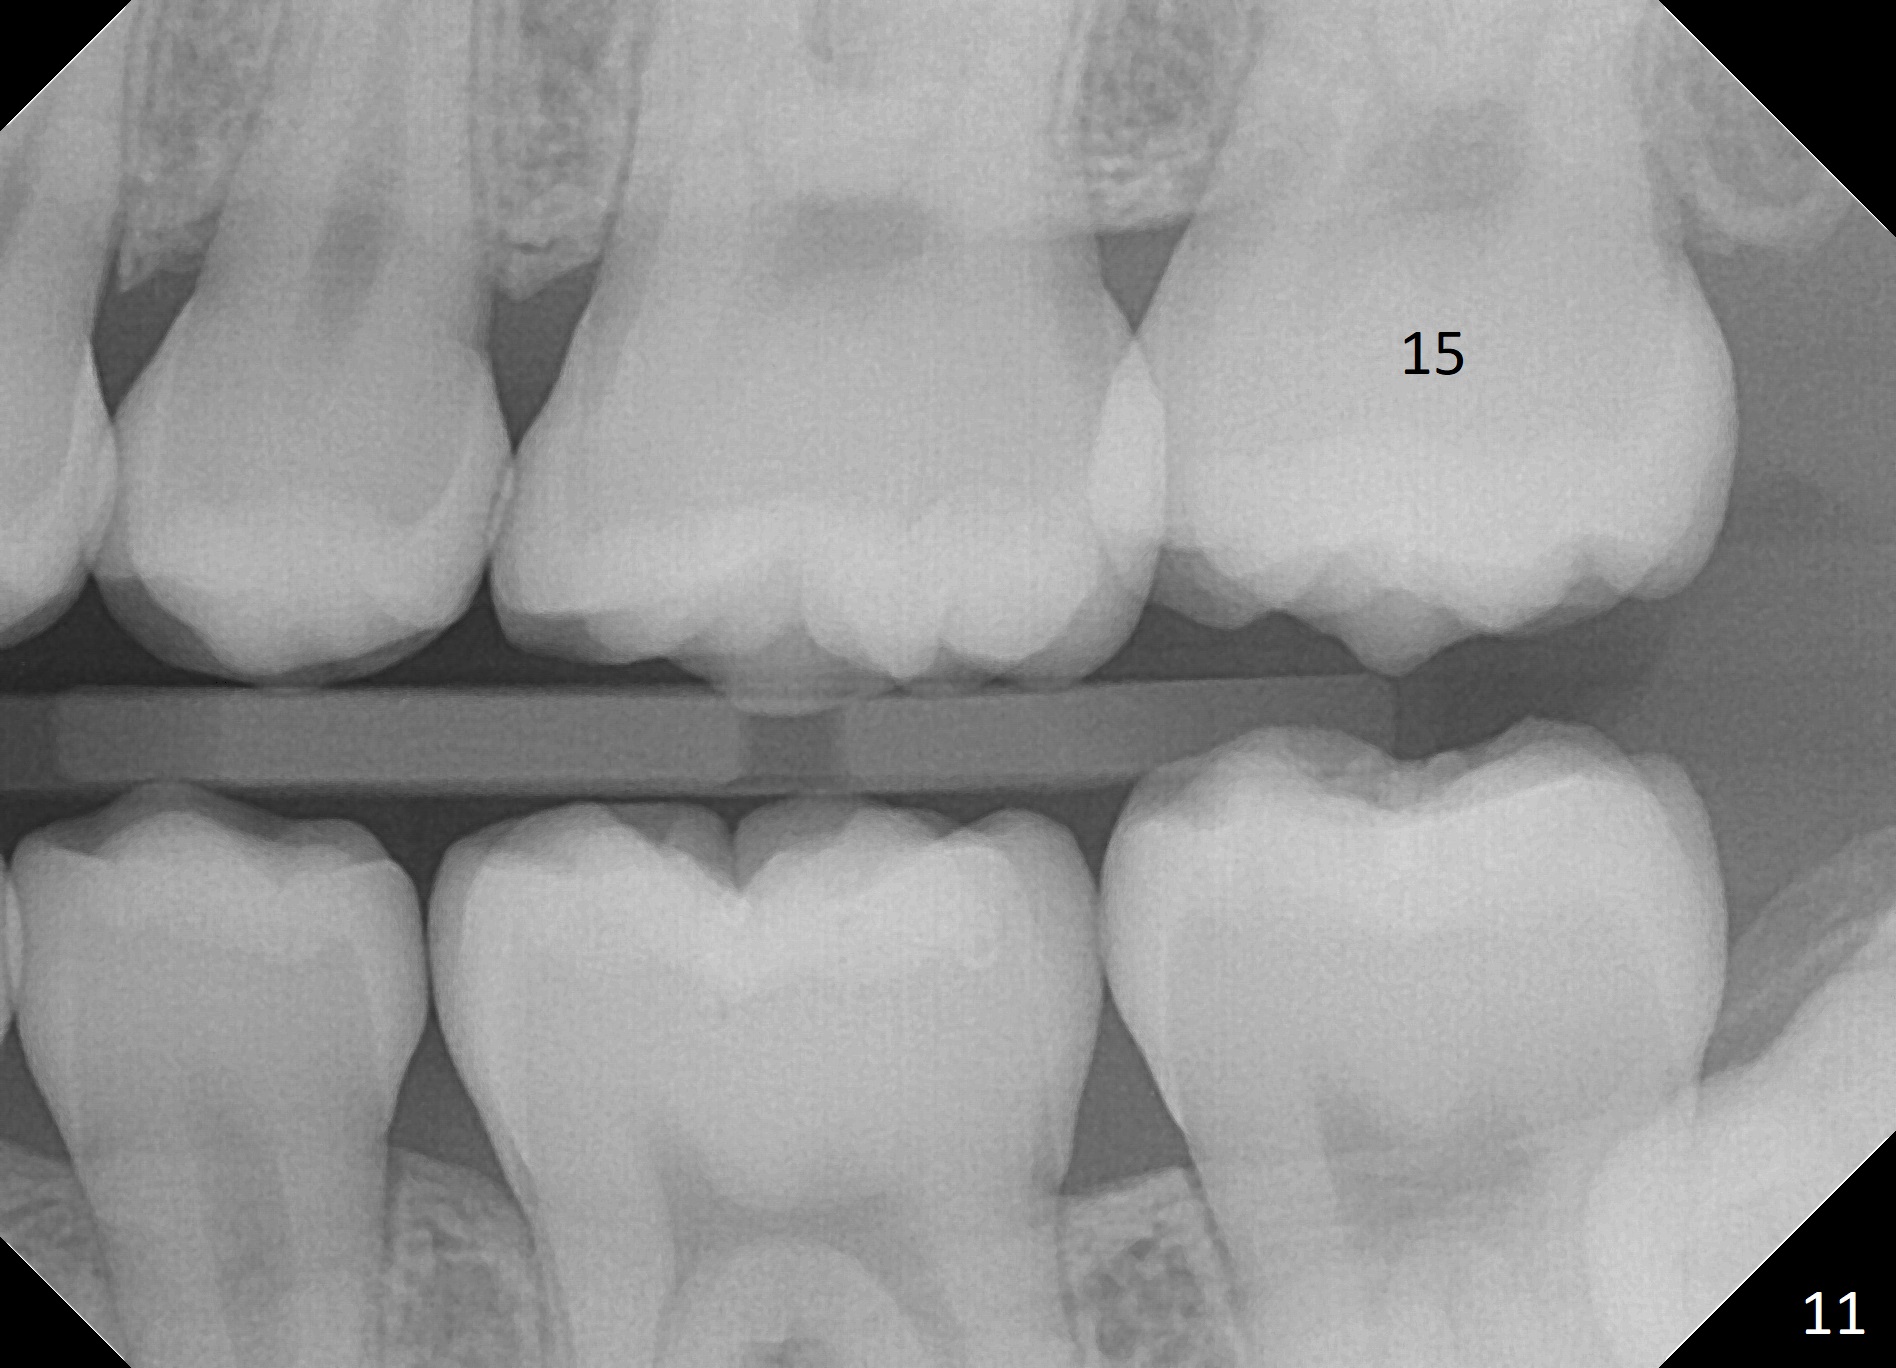

The distobuccal cusp of the tooth is subgingival 8 months post banding (Fig.6 (mirror view) *). A 2nd surgery is performed to expose the gold chain (Fig.7 <) and a bracket is placed. With arch wires, eruption of the impacted tooth is quickened (Fig.8). Later a 3rd minor surgery is done to place a lingual button to facilitate lingual cusp eruption. Finally a band has to be placed at #15. Treatment finishes in 2 years. The patient (15 years 2 months old) returns for follow up 3 months post debanding (Fig.9). There is no bone loss around the tooth #15 2 years 4 months post de-banding (Fig.11, as compared to the tooth #2 (Fig.10)).